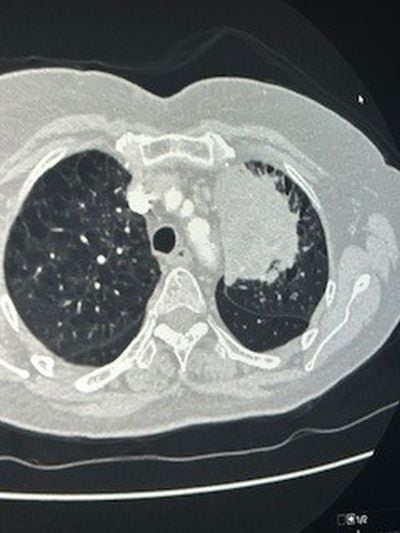

Στις φωτογραφίες 1 και 2 φαίνεται μεγάλος όγκος αριστερού πνεύμονος που εμφάνισε απόστημα και σηψαιμία. Οι λεμφαδένες που κατεγράφησαν στην αξονική και στο Pet Scan χαρακτηρίστηκαν καρκινικοί λεμφαδένες και το περιστατικό είχε χαρακτηριστεί ανεγχείρητο. Μια γενναία απόφαση της ομάδας μας, οδήγησε τον ασθενή σε αριστερή πνευμονεκτομή, όλοι οι λεμφαδένες ήταν αρνητικοί για κακοήθεια (ήταν έντονα φλεγμονώδεις και έδιναν ψευδή εικόνα) και κανένα από τα υπόλοιπα όργανα δεν είχαν διηθηθεί παρά τη γειτνίαση με τον όγκο (αορτή, μεσοθωράκιο, τραχεία). Η ασθενής είναι σε άριστη κατάσταση και είναι σε πρώτο κύκλο χημειοθεραπείας.